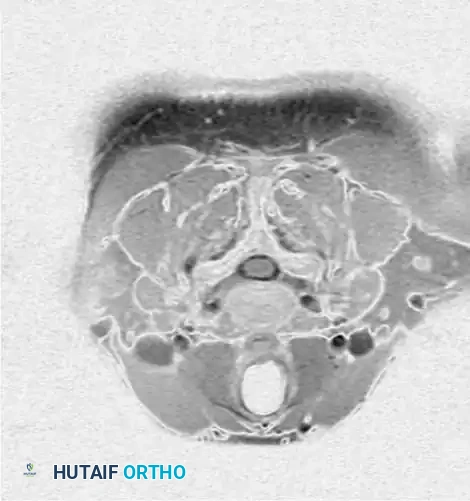

Fig. 39-6 D: Postmyelogram CT axial cut. The introduction of intrathecal contrast provides stark differentiation between the thecal sac, nerve roots, and surrounding osseous structures.

Fig. 39-6 E: Postmyelogram CT clearly revealing a right intraforaminal disc herniation compressing the exiting C7 nerve root, which was missed on the initial MRI.